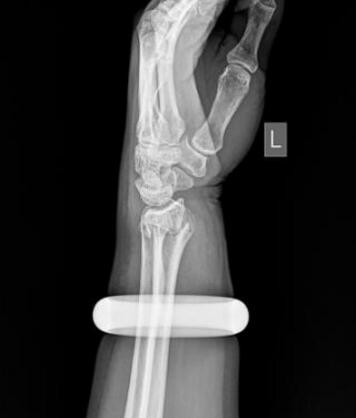

雪天摔倒手腕骨折,在邻居建议下跑去按摩,不料手腕越肿越厉害,2万元玉镯深陷肉里。为保住手臂,王阿姨“狠心”砸碎玉镯,顺利接受了手法复位。

25日早上,57岁的王女士买菜回家时不慎滑倒,情急之下她用左手撑地,很快手腕就肿了起来。邻居听说后,让她赶紧去做做按摩,结果越按越痛,越肿越厉害。下午她找到武汉市第一医院骨科门诊,拍片发现左手桡骨远端骨折。

玉镯贴身戴了七八年,当年花了2万元买的。思虑再三,王女士提出砸碎玉镯,并签字为证。石晨用叩诊锤敲碎了镯子后,当即为她手法复位,打上了石膏。